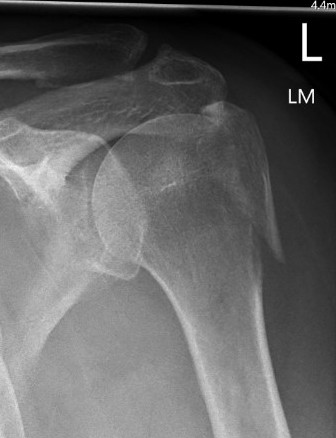

Three part

Three part with greater tuberosity fracture

Three part fracture dislocation anterior

Three part fracture dislocation with anatomical neck

Three part head splitting fracture